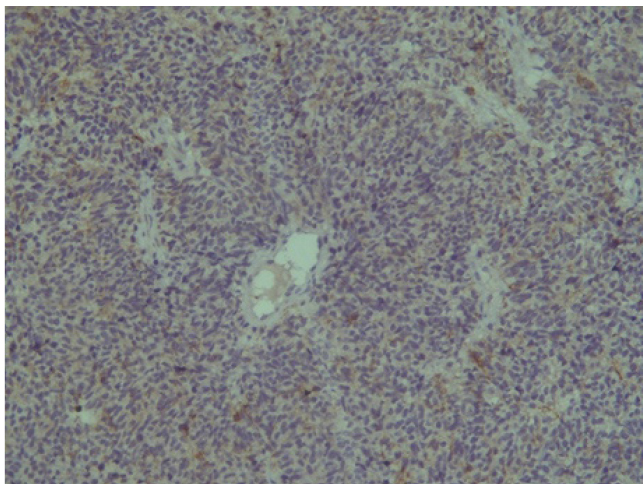

Поэтому при первичном гистологическом исследовании диагноз эстезионейробластомы был установлен только у 6 пациентов (66,6 %), у троих больных (33,4 %) были диагностированы другие формы злокачественного процесса, что не соответствовало клиническим проявлениям. Во всех случаях проводили иммуногистохимическое (ИГХ) исследование. ИГХ-исследование проводили на срезах с парафиновых блоков с использованием антител к Keratin.Pan (AE/AE3), CD45 (Cocktail), Synaptophysin (SP11), ChromograninA (SP12), CD56 (56C04), Ki-67 (30-9), p63 (7JUL)RTU, S100, INI1, CD99 (HO36-1.1). Также выполняли доставку с антителами к EMA (E29), TTF1 (8G7G3/1). В диагностических материалах была отмечена положительная экспрессия Synaptophysin, ChromograninA, CD56, Ki-67 (до 90% ядер), INI1 (рис. 2–6).

Рис. 2. Synaptophysin [SP 11] ×200

Рис. 3. Chromagranin A [SP 12] ×200

Рис. 4. CD 56 [56C04] ×200

Рис. 5. Ki-67 [30-9] (90%) ×200

Рис. 6. INI 1 ×200

Эти результаты иммуногистохимического исследования подтверждают наибольшее соответствие иммунофенотипа опухоли – ольфакторной нейробластоме (G3 по Hyams) М9522/33.